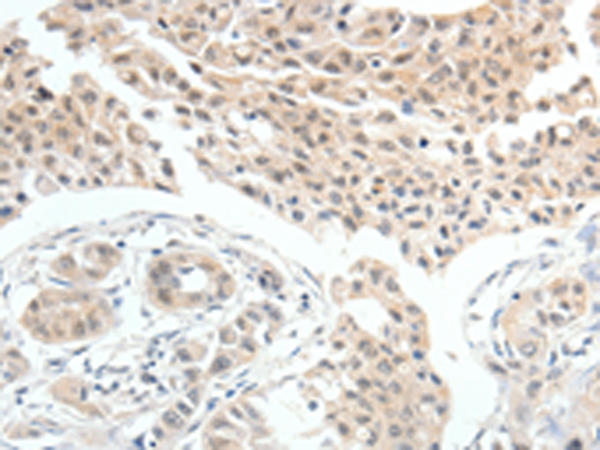

分类: 科研抗体货号: P00534别名: MI; WS2; CMM8; WS2A; COMMAD; bHLHe32应用: WB,IHC反应种属: Human, Mouse, Rat